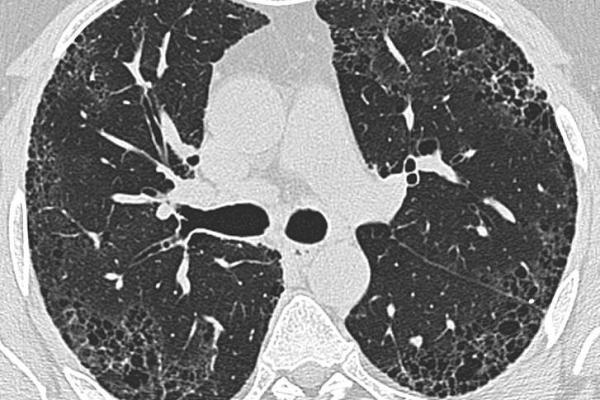

İPF belirtilerinin astım ve KOAH (Kronik Obstrüktif Akciğer Hastalığı) gibi hastalıklarla karışmasına neden olabildiğine işaret eden Prof. Dr. Okutan, bu noktada ayırıcı tanının önemine dikkat çekti. Prof. Dr. Okutan, şu değerlendirmeyi yaptı: “İPF tanısı, hastalığın akciğerde oluşturduğu sertleşmeyi yapabilecek mesleki ve çevresel hastalıklar, ilaçlar, romatizmal hastalıklar gibi nedenler elendikten sonra görüntüleme yöntemlerinde İPF’ye özgü tipik bulguların görülmesiyle konuluyor. Tanıda detaylı öykü, fizik muayene, romatizmal hastalıkların dışlanması için bazı kan tahlilleri, gerek duyulması halinde romatoloji görüşü ve deneyimli radyoloji uzmanları tarafından yorumlanan yüksek çözünürlüklü akciğer tomografisi gibi yöntemler kullanılıyor. Tipik bulguların olmadığı durumlarda ise akciğer biyopsisine başvuruluyor. Hastalığın seyrinin takip edilmesinde de solunum fonksiyon testleri, altı dakika yürüme testi ve ekokardiyografi gibi testlerden de yararlanılıyor. Erken tanı sayesinde akciğer fonksiyonlarında ileri düzeyde kayıp ortaya çıkmadan tedaviye başlanabiliyor.”